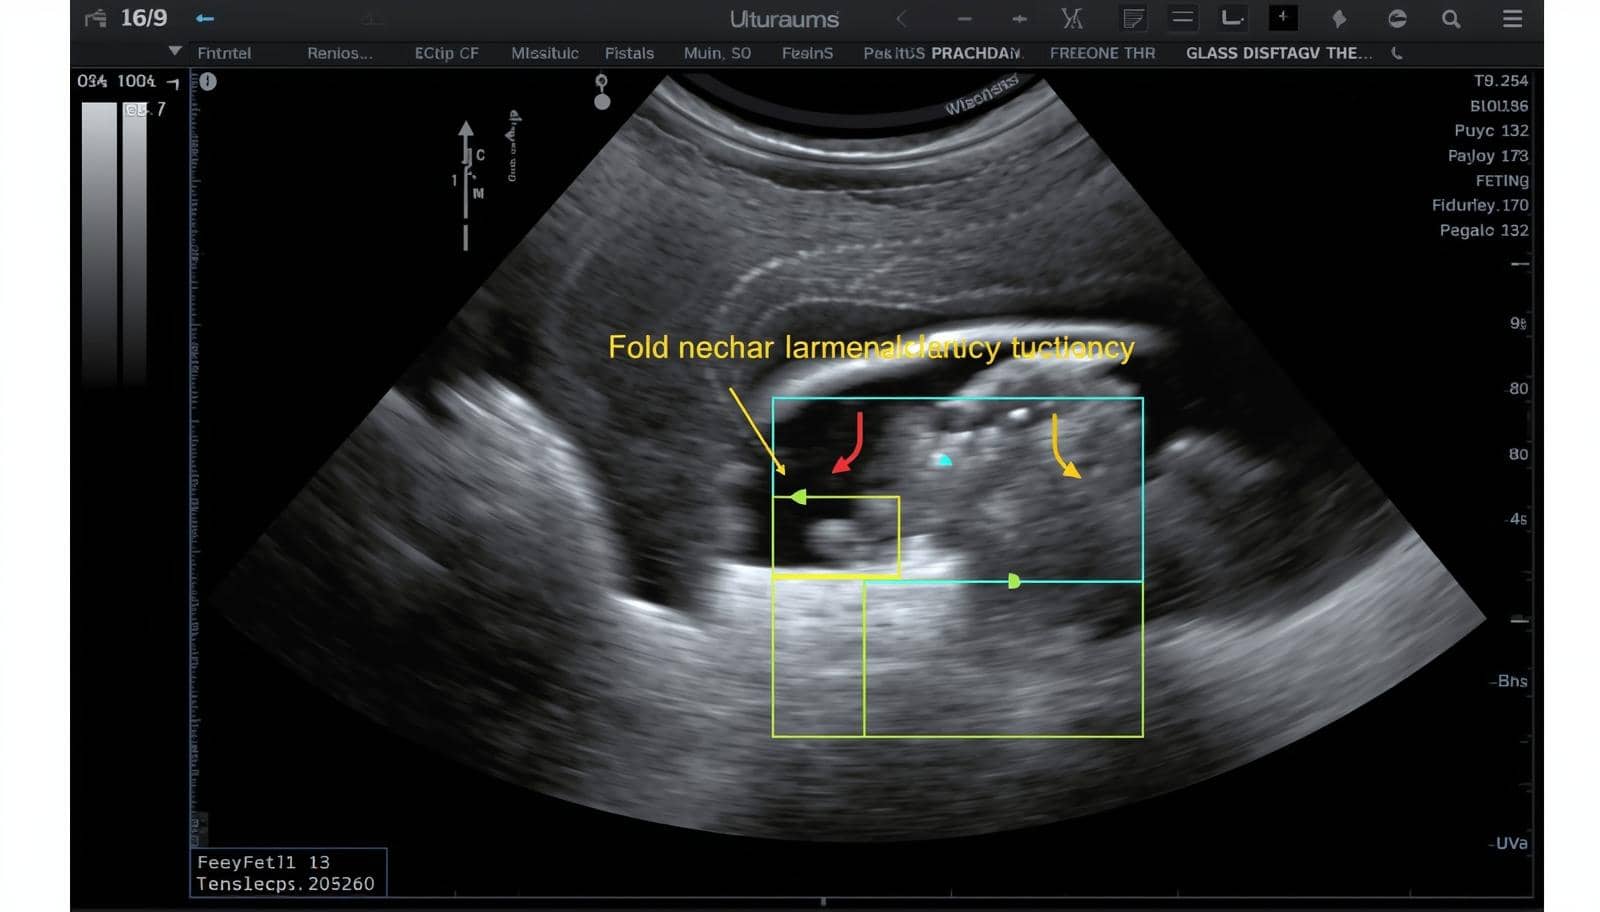

photo d'une échographie montrant un foetus avec trisomie 21 : Emmanuel-SOS-Adoption